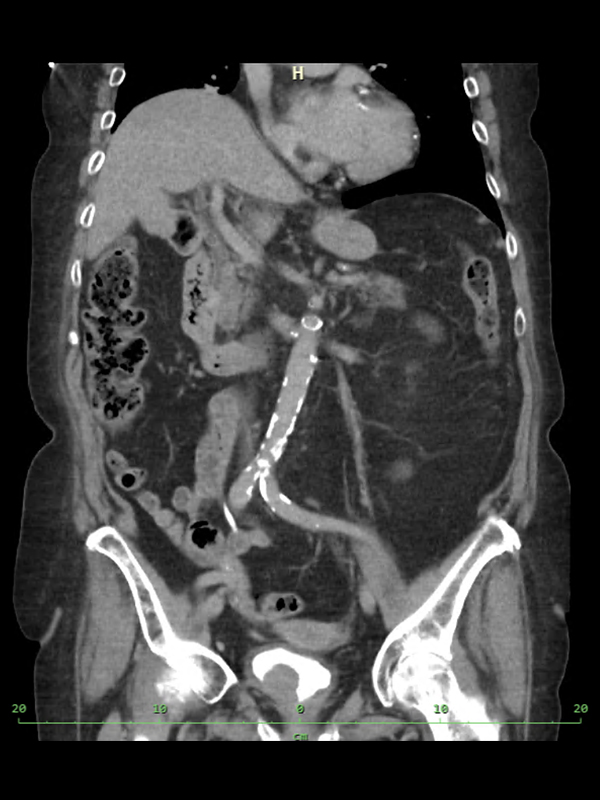

Počítačová tomografie (CT) s kontrastní látkou

- pavilon B5

- datum a čas určí lékař

- lačnost 4 hodiny

- žádanka vystavena elektronicky